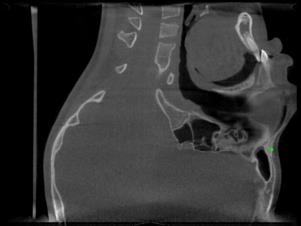

Detecting 3D landmarks on cone-beam computed tomography (CBCT) is crucial to assessing and quantifying the anatomical abnormalities in 3D cephalometric analysis. However, the current methods are time-consuming and suffer from large biases in landmark localization, leading to unreliable diagnosis results. In this work, we propose a novel Structure-Aware Long Short-Term Memory framework (SA-LSTM) for efficient and accurate 3D landmark detection. To reduce the computational burden, SA-LSTM is designed in two stages. It first locates the coarse landmarks via heatmap regression on a down-sampled CBCT volume and then progressively refines landmarks by attentive offset regression using multi-resolution cropped patches. To boost accuracy, SA-LSTM captures global-local dependence among the cropping patches via self-attention. Specifically, a novel graph attention module implicitly encodes the landmark's global structure to rationalize the predicted position. Moreover, a novel attention-gated module recursively filters irrelevant local features and maintains high-confident local predictions for aggregating the final result. Experiments conducted on an in-house dataset and a public dataset show that our method outperforms state-of-the-art methods, achieving 1.64 mm and 2.37 mm average errors, respectively. Furthermore, our method is very efficient, taking only 0.5 seconds for inferring the whole CBCT volume of resolution 768$\times$768$\times$576.